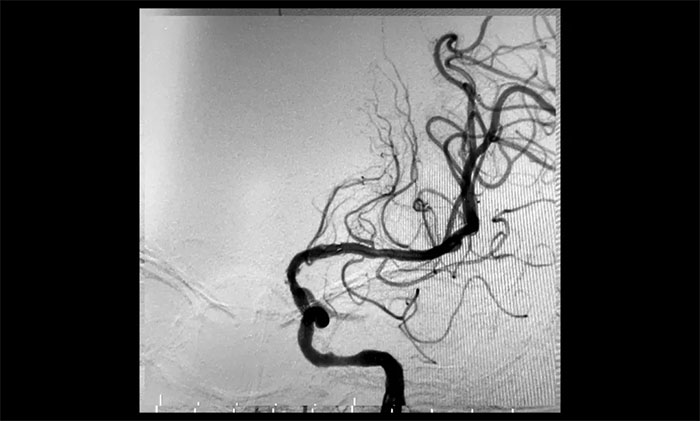

▲ 左颈内动脉起始段重度狭窄,并串联多处狭窄、闭塞

双侧颈内动脉起始段狭窄90%,并且左侧颈动脉属于串联病变。根据患者临床症状及造影结果,席刚明教授、王贵平博士考虑患者双侧大脑半球血流明显灌注不足,属于卒中高危病人,如不开通颈内动脉,反复脑梗死风险极高。但是,如果同时处理两侧颈动脉发生高灌注综合症风险高。

术后一个月,经过综合治疗,患者病情稳定。10月11日,再次行经皮左侧颈动脉慢性闭塞开通术,脑保护伞下左侧颈动脉支架置入手术,经皮左侧颈动脉球囊扩张成形术。术中造影显示,左颈内动脉起始段多发重度狭窄,左颈内动脉前向血流慢,左颈内动脉岩骨段中度狭窄,左颈内动脉眼动脉段、后交通段多发重度狭窄伴次全闭塞。

经微导丝成功进入狭窄、闭塞颈内动脉,在支架保护下,进行球囊逐段扩张,支架置入……,经多次球囊扩张,置入支架后,造影显示左颈内动脉起始段狭窄明显改善,左颈内动脉颅内段顺利再通,左颈内动脉眼动脉段、后交通段狭窄明显改善。造影及3D造影见左颈总动脉、左颈内动脉、左大脑中动脉显影可,行支架CT见颅内支架成形可,手术取得成功!

▲术后,左颈内动脉起始段狭窄明显改善,左颈内动脉颅内段顺利再通,左颈内动脉眼动脉段、后交通段狭窄明显改善